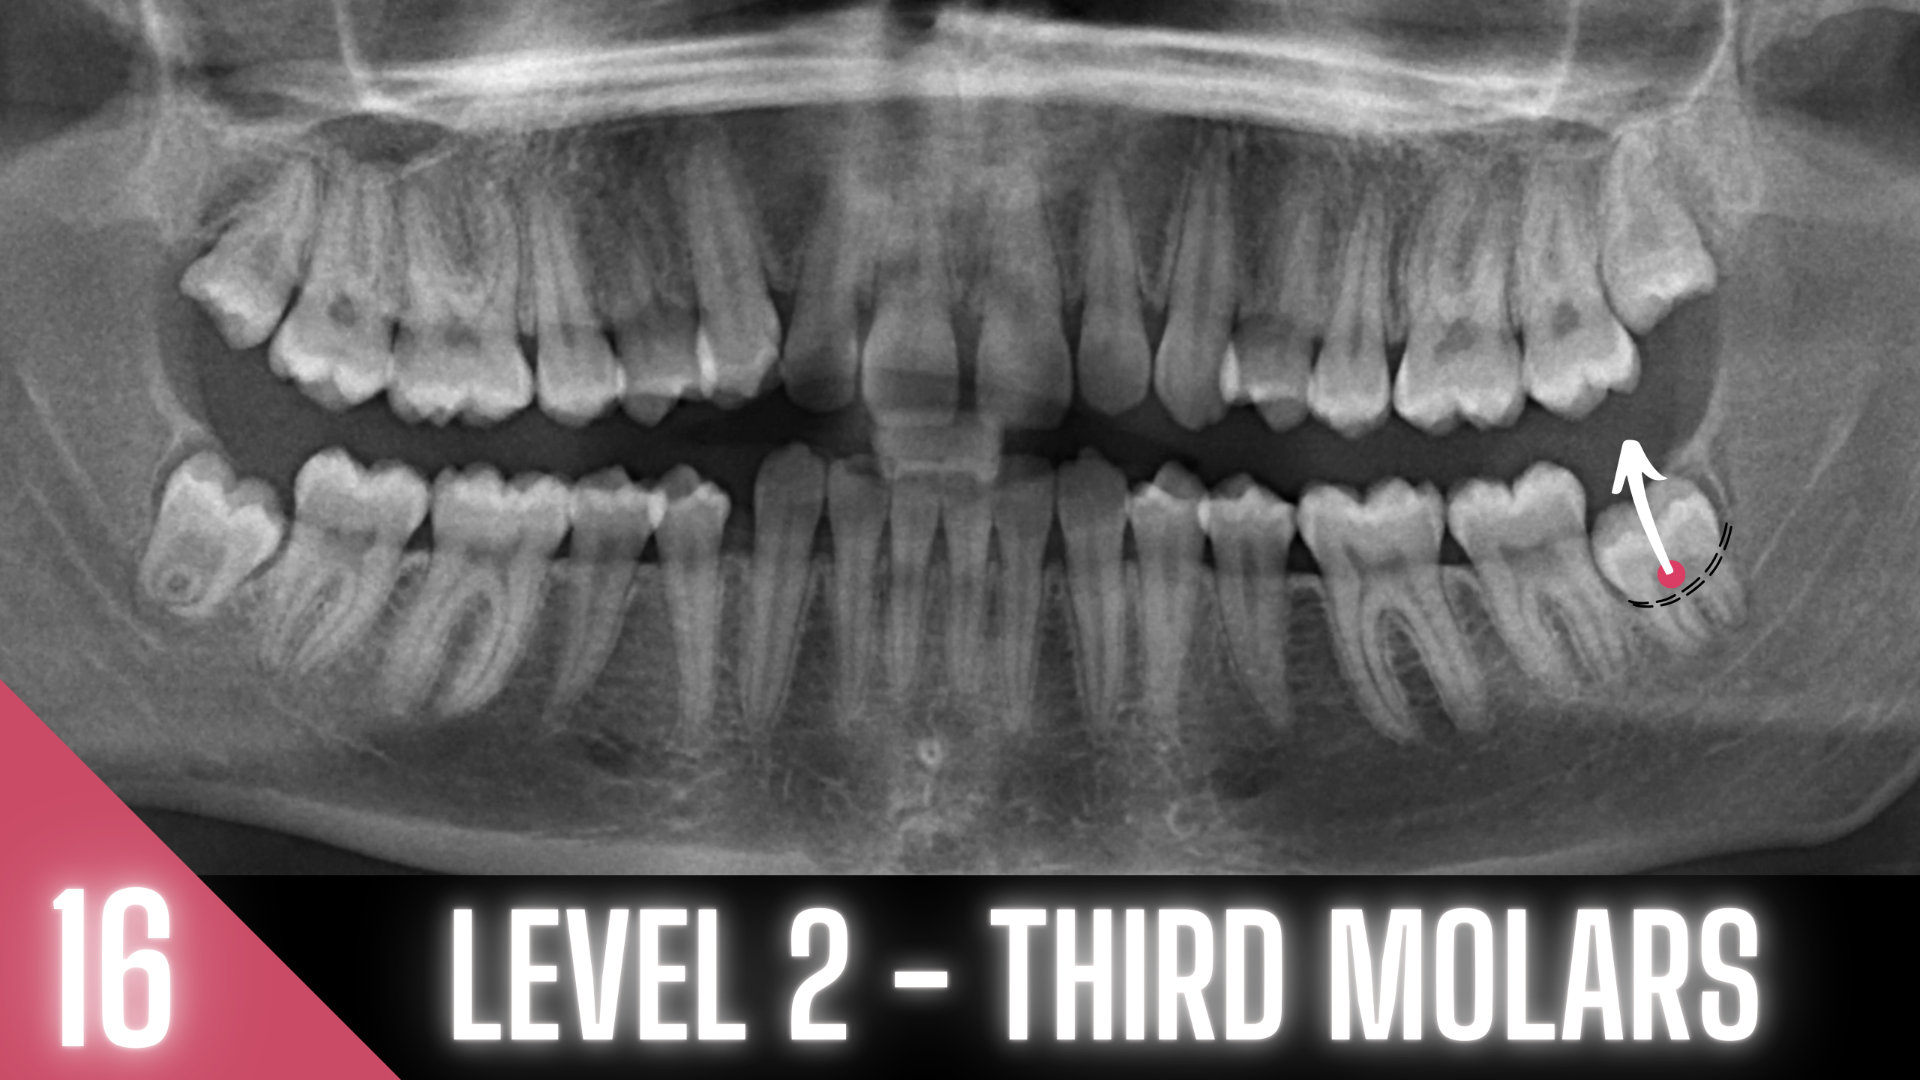

20 MODULES TO MASTER EXODONTIA

Everything you will ever need to know to master exodontia!